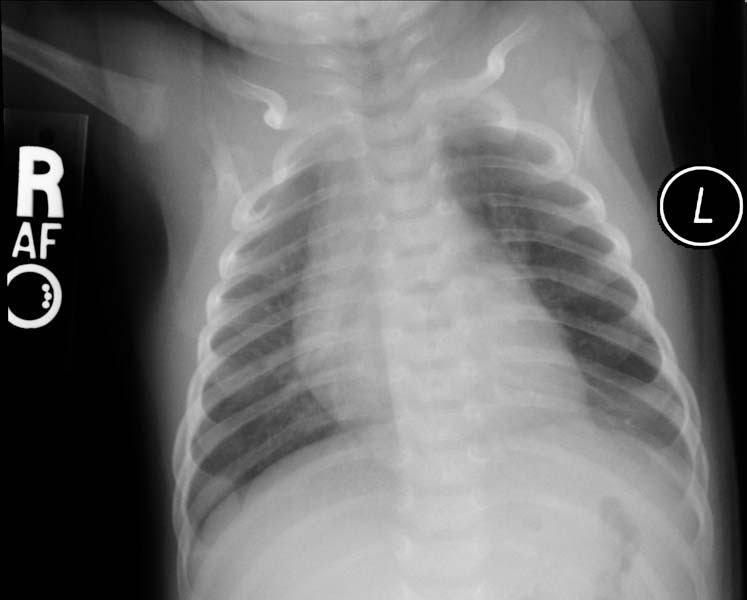

Рентгеновские снимки при врожденной эмфиземе легкого

Раздел: Визуальные уроки